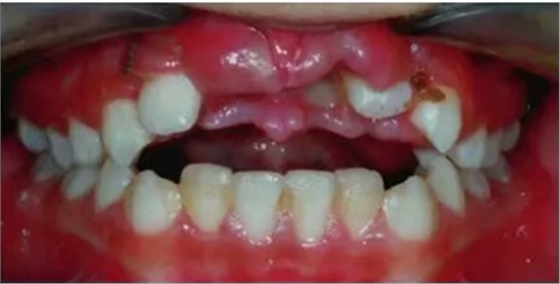

六年和十三年的隨訪顯示移植牙的情況是正常的。移植牙在臨床上是有活力的,影像學(xué)是正常的,沒(méi)有出現(xiàn)髓腔鈣化,也沒(méi)有根骨粘連或牙根吸收的跡象和癥狀(圖7和圖8)。雖然移植牙的牙周膜和牙髓活力都是正常的,但是他們的牙根發(fā)育和冠/根比并不相似。移植牙與鄰牙的牙槽嵴高度相同。

然而,由于移植牙之間較大的間隙,中線處存在吸收的區(qū)域。年齡增長(zhǎng)之后可以進(jìn)行口腔修復(fù)治療或牙周美學(xué)手術(shù)。

圖7. 6年隨訪口內(nèi)照及影像學(xué)檢查